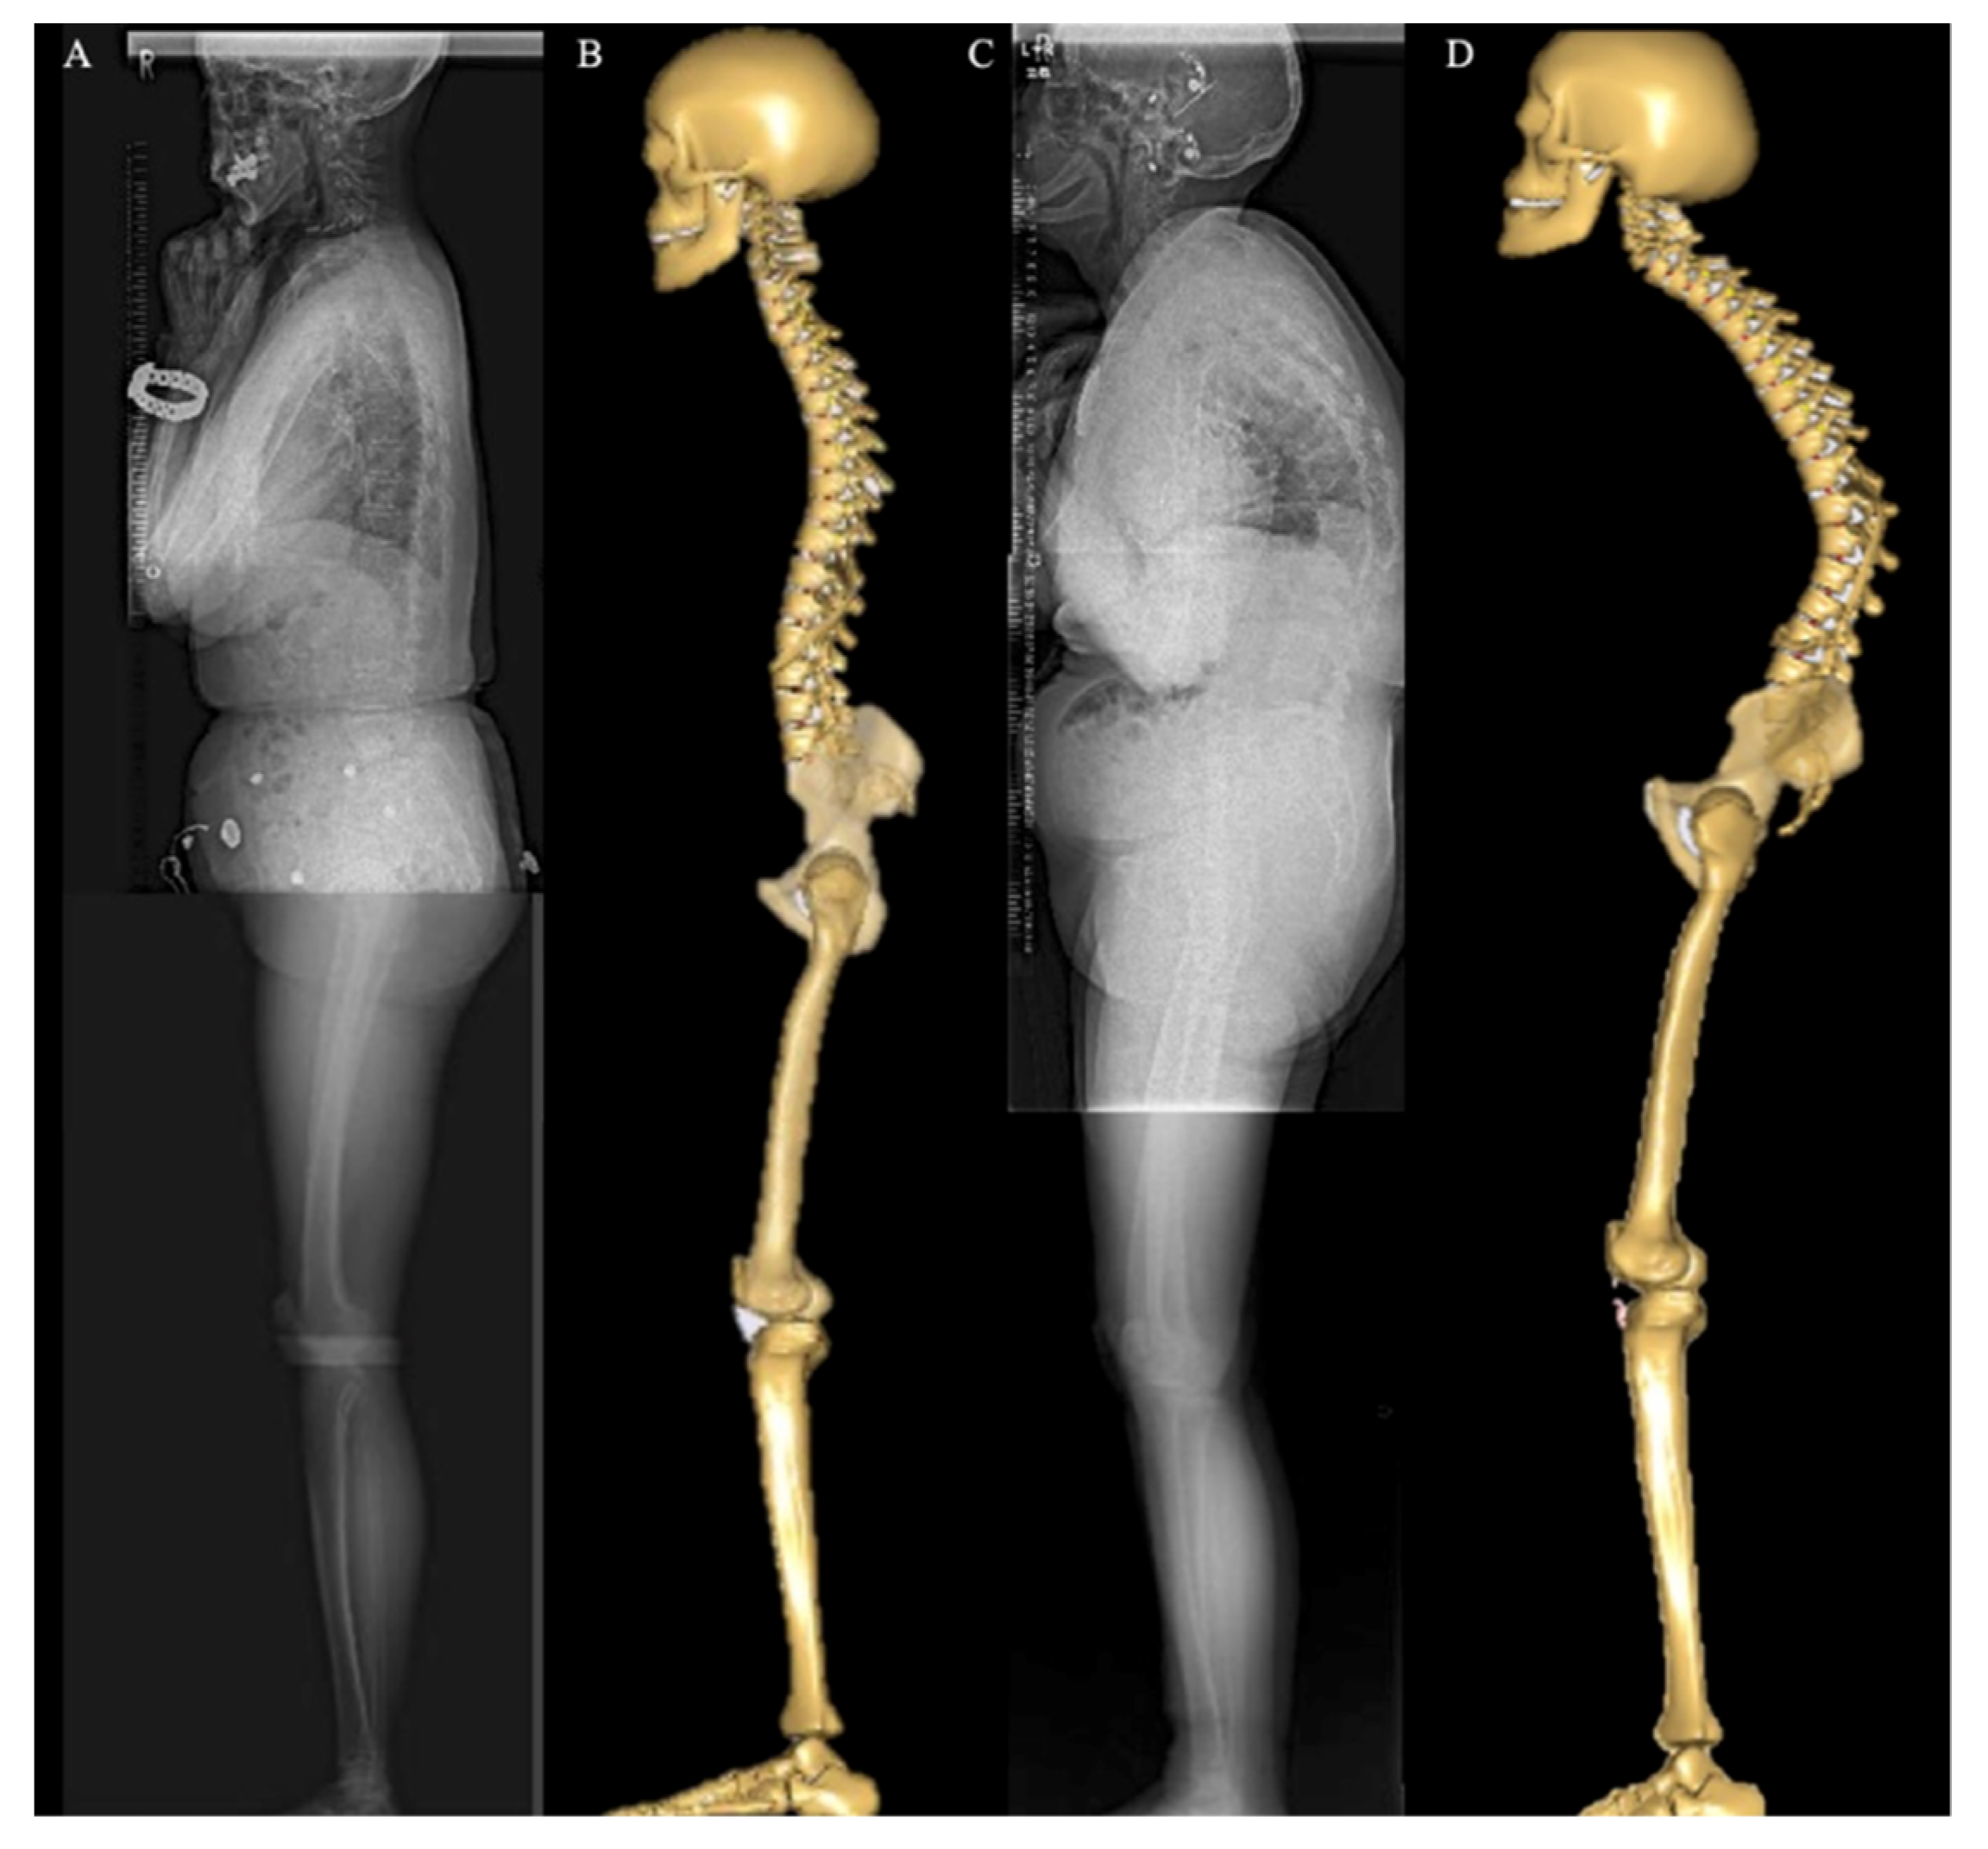

2.3. Musculoskeletal Model

2.4. Spinopelvic and Lower-Extremity Sagittal Alignment Input and Simulation Process

- Miura, T.; Miyakoshi, N.; Saito, K.; Kijima, H.; Iida, J.; Hatakeyama, K.; Suzuki, K.; Komatsu, A.; Iwami, T.; Matsunaga, T.; et al. Association between global sagittal malalignment and increasing hip joint contact force, analyzed by a novel musculoskeletal modeling system. PLoS ONE 2021, 16, e0259049. [Google Scholar] [CrossRef]